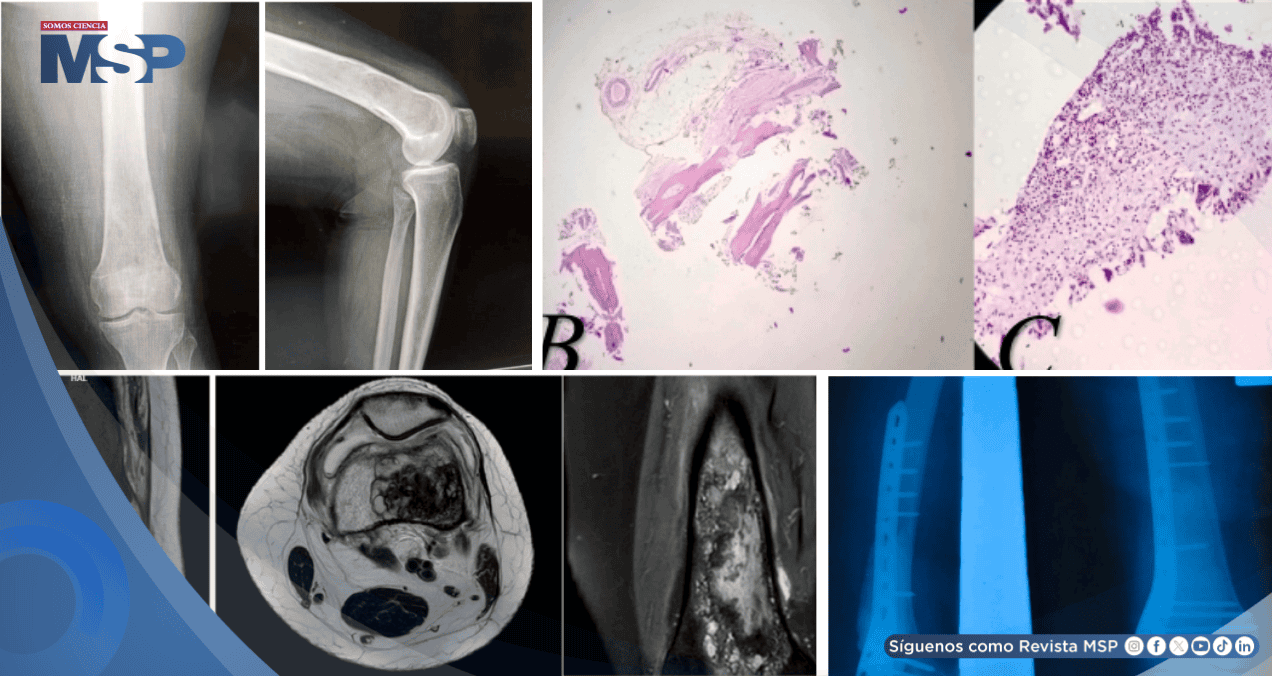

Las radiografías simples en proyecciones anteroposterior y lateral revelaron una lesión lítica mal definida, no destructiva, en la región distal del fémur. Ante este hallazgo, se plantearon como diagnósticos diferenciales iniciales un quiste óseo simple, un quiste óseo aneurismático o un fibroma condromixoide.

Se solicitó una resonancia magnética que mostró una lesión bien delimitada, heterogénea, de aspecto no agresivo, con dimensiones de 7 × 4 × 3 centímetros. La lesión presentaba baja señal en secuencias ponderadas en T1 y señal mixta en T2 y densidad protónica.

El estudio histopatológico de la muestra obtenida reportó tejido óseo benigno con tejido fibroso interpuesto y la presencia de células gigantes multinucleadas, hallazgos que, correlacionados con las imágenes, sugerían un quiste óseo aneurismático.

El tejido resecado fue enviado nuevamente para análisis histopatológico. El estudio reveló fragmentos de tejido óseo y tejido fibrótico inflamado con formación de tejido de granulación, así como fragmentos de material laminado acelular de color rosado, compatible con la capa germinativa de un quiste hidatídico. El diagnóstico definitivo fue, entonces, quiste hidatídico óseo.